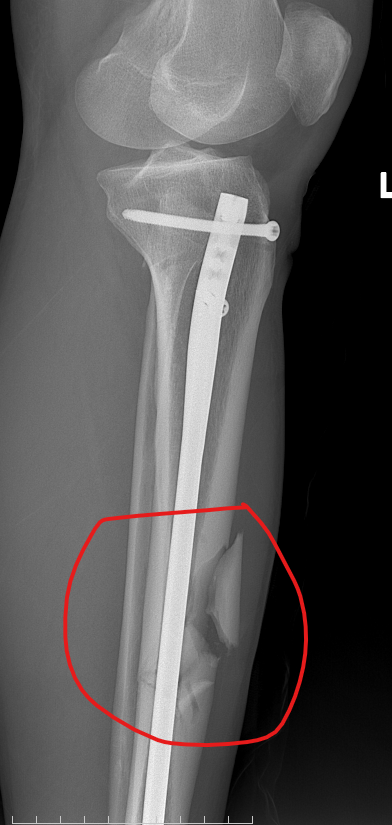

患者术后影像图片

患者为72岁藏族男性,因摔伤导致左胫骨中下段骨折。面对高龄、骨质疏松、骨折不稳定等多重挑战,若沿用传统手术方式,不仅复位难度大,术后恢复也面临较高风险。在宁波大学附属人民医院援藏专家朱峰老师的带领下,骨科团队经过深入讨论,决定采用目前国内外先进的“髌上入路髓内钉内固定术”。该术式创伤小、固定牢靠、恢复快,尤其适合高原地区的老年患者。

然而,木里县地处高原偏远地区,医疗资源相对薄弱,此类手术此前从未开展。在“组团式”帮扶机制的支持下,朱峰老师带领本地医护团队,从术前模拟、术中操作到术后康复,开展全流程带教。2025年11月4日,在陈宗义主任主刀、朱峰老师现场指导下,手术顺利完成,全程仅75分钟,出血不足50毫升,术后患者恢复良好,第五天即顺利出院。